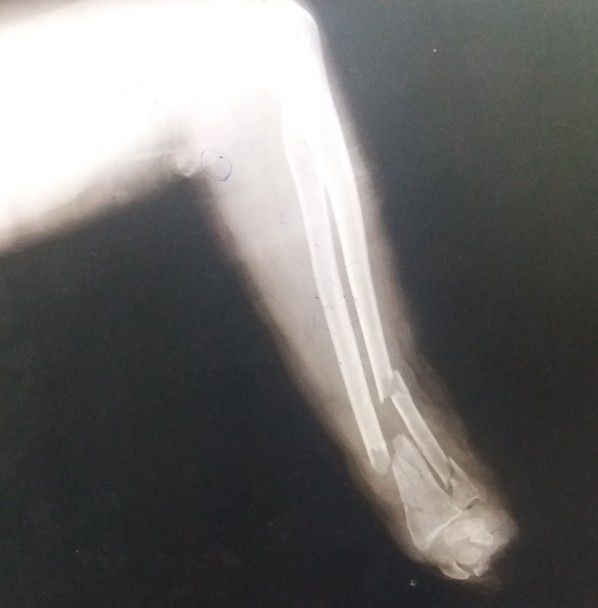

A woman of about 48 yrs old was received in ER with the c/o toka injury on the arm about 30 minites ago.. On gross examination no fingers or hand was found . muscles of the firearm were completely transected (multiple times) n underlying bone could b seen. Nerves and vessel were damaged . Wound was dirty and remains of fodder could be seen. Xray showed both radius and ulnar fracture, radius was completely fractured and ulna was fractured at two points (shaft and distal end). Patient was immediately given fluids, antibiotics, transamine and painkillers via iv line; was stabilized blood arranged and moved to ESOT for amputation(L.A.E.A) After the surgery pt was observed for one day and was discharged the next day to follow up after a week.